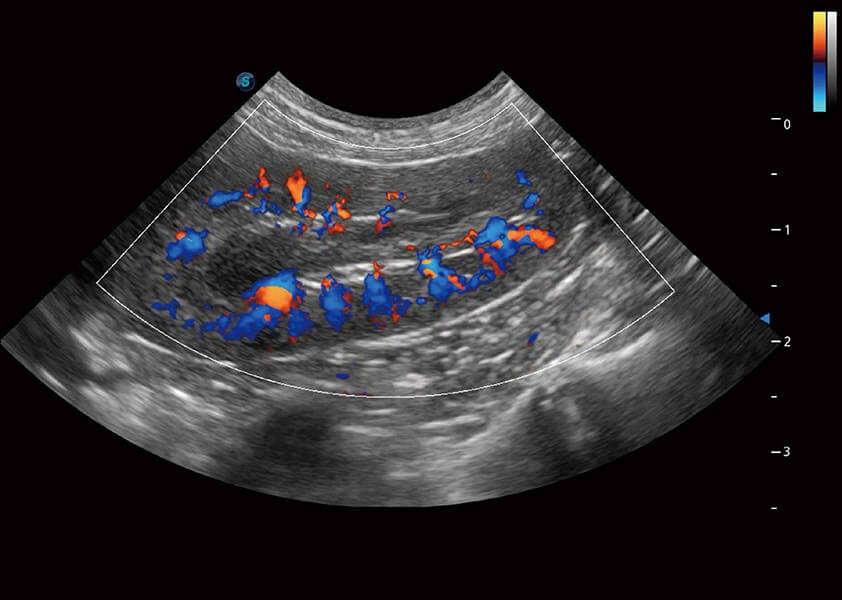

ProPet 60 作為一款高端臺式動物超聲設備,為動物醫(yī)生的日常診斷提供了一系列貼合動物臨床需求、解決臨床實際問題的高級成像功能。憑借全系列高清探頭,滿足醫(yī)生對腹部、心臟、生殖、淺表、肌骨等成像的所有需求,切實幫助您提升檢查效率,提高診斷信心。

獸用彩色多普勒超聲診斷系統(tǒng)